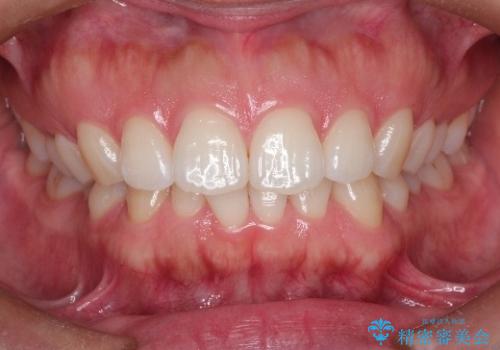

ディープバイトをインビザライン矯正で改善